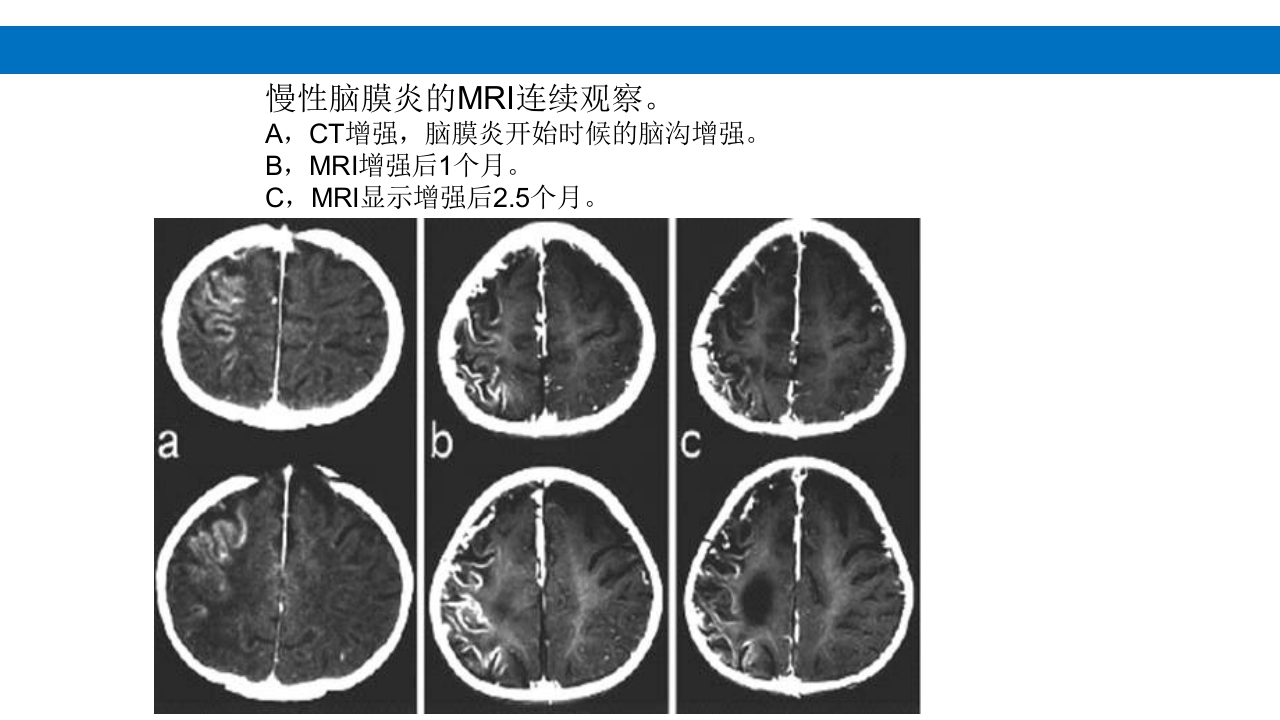

颅脑损伤的并发症及后遗症 讲解人:xxx 20XX年x月x日 1.颅骨骨髓炎 病因:为头皮软组织、中耳、乳突和副鼻窦等处炎性感染而经导 血管侵入颅骨内或颅脑开放伤感染所引起,亦可由菌血症后发生 的细菌栓子由血运转移至颅骨内。 影像学表现: 头部CT: 1.表现为不规则的蜂窝状骨质破坏区,主要位于板障,亦可累 及内外板。 2.破坏区内可见高密度的米粒状细小的高密度死骨。 3.周边可见骨质硬化增生,颅板外无骨膜反应。 4.局部的头皮可见软组织肿胀。 头部MRI: 由于受累部位细胞成分和水量增多,T1WI为低信号, T2WI为高信号,急性期边界不清,慢性期病灶局限, 边界清晰。MRI显示骨质破坏没有CT效果好。 治疗: 除应用抗菌药物控制感染外,当感染局限或已有死骨形成后, 应行手术切除感染...